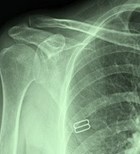

היי רציתי בבקשה לשאול 2 שאלות לגבי בעלי, בעלי בן 68 עם רקע של סכרת, לב, cva ויש לו קרע בכתף שהובחנה ע"י אולטרסאונד נאמר לנו שאין מה לעשות אלא להתמודד עם הכאב, הדבר מגביל אותו מאוד בתנועה וגורם לו לכאבים עזים האם יש משהו שכן ניתן לעשות?? ושאלה שניה יש לו מחלת דופיטרן בכף היד בהתחלה חד משמעית הומלץ על ניתוח אך בעקבות ההסטוריה הרפואית הומלץ לאחר התלבטות על זריקת xiapex מה הגורמי סיכון בזריקה? והאם אכן זה הפתרון האידאלי עבורו?

חן שלום, 1. לגבי הכתף - בגילו לרוב מדובר בקרע ניווני של גידי הכתף ולכן פיזיותראפיה ונוגדי כאב הינם הטיפול הראשוני המומלץ. אם לאחר זאת עדיין יש מגבלה וכאב, אז יש לשקול ניתוח כאשר צריכים להילקח בחשבון הסיכונים בשל מחלות הרקע שלו 2. לגבי XIAPEX - היום זהו הקו הראשון בטיפול בדיופטרן והינו יכול להוות פתרון מצויין ללא ניתוח, אך קיים סיכוי לחזרת המחלה בטווח של מספר שנים (בגדול כ-50% מהחולים לאחר זריקה, יש חזרה תוך 5-7 שנים). הסיכונים הינם קרעים בעור שמתאחים ללא קושי, פגיעה בעצבים הנותנים תחושה לאצבעות או בגידים שמכופפים אותם. כששוקלים זאת מול הסיבוכים בניתוח ובהרדמה כללית עבור חולה עם מחלות רקע משמעותיות, הרי שזריקה שנעשית באופן אמבולטורי במסגרת מרפאה הינה פתרון הולם. בברכה, ד"ר יהודה